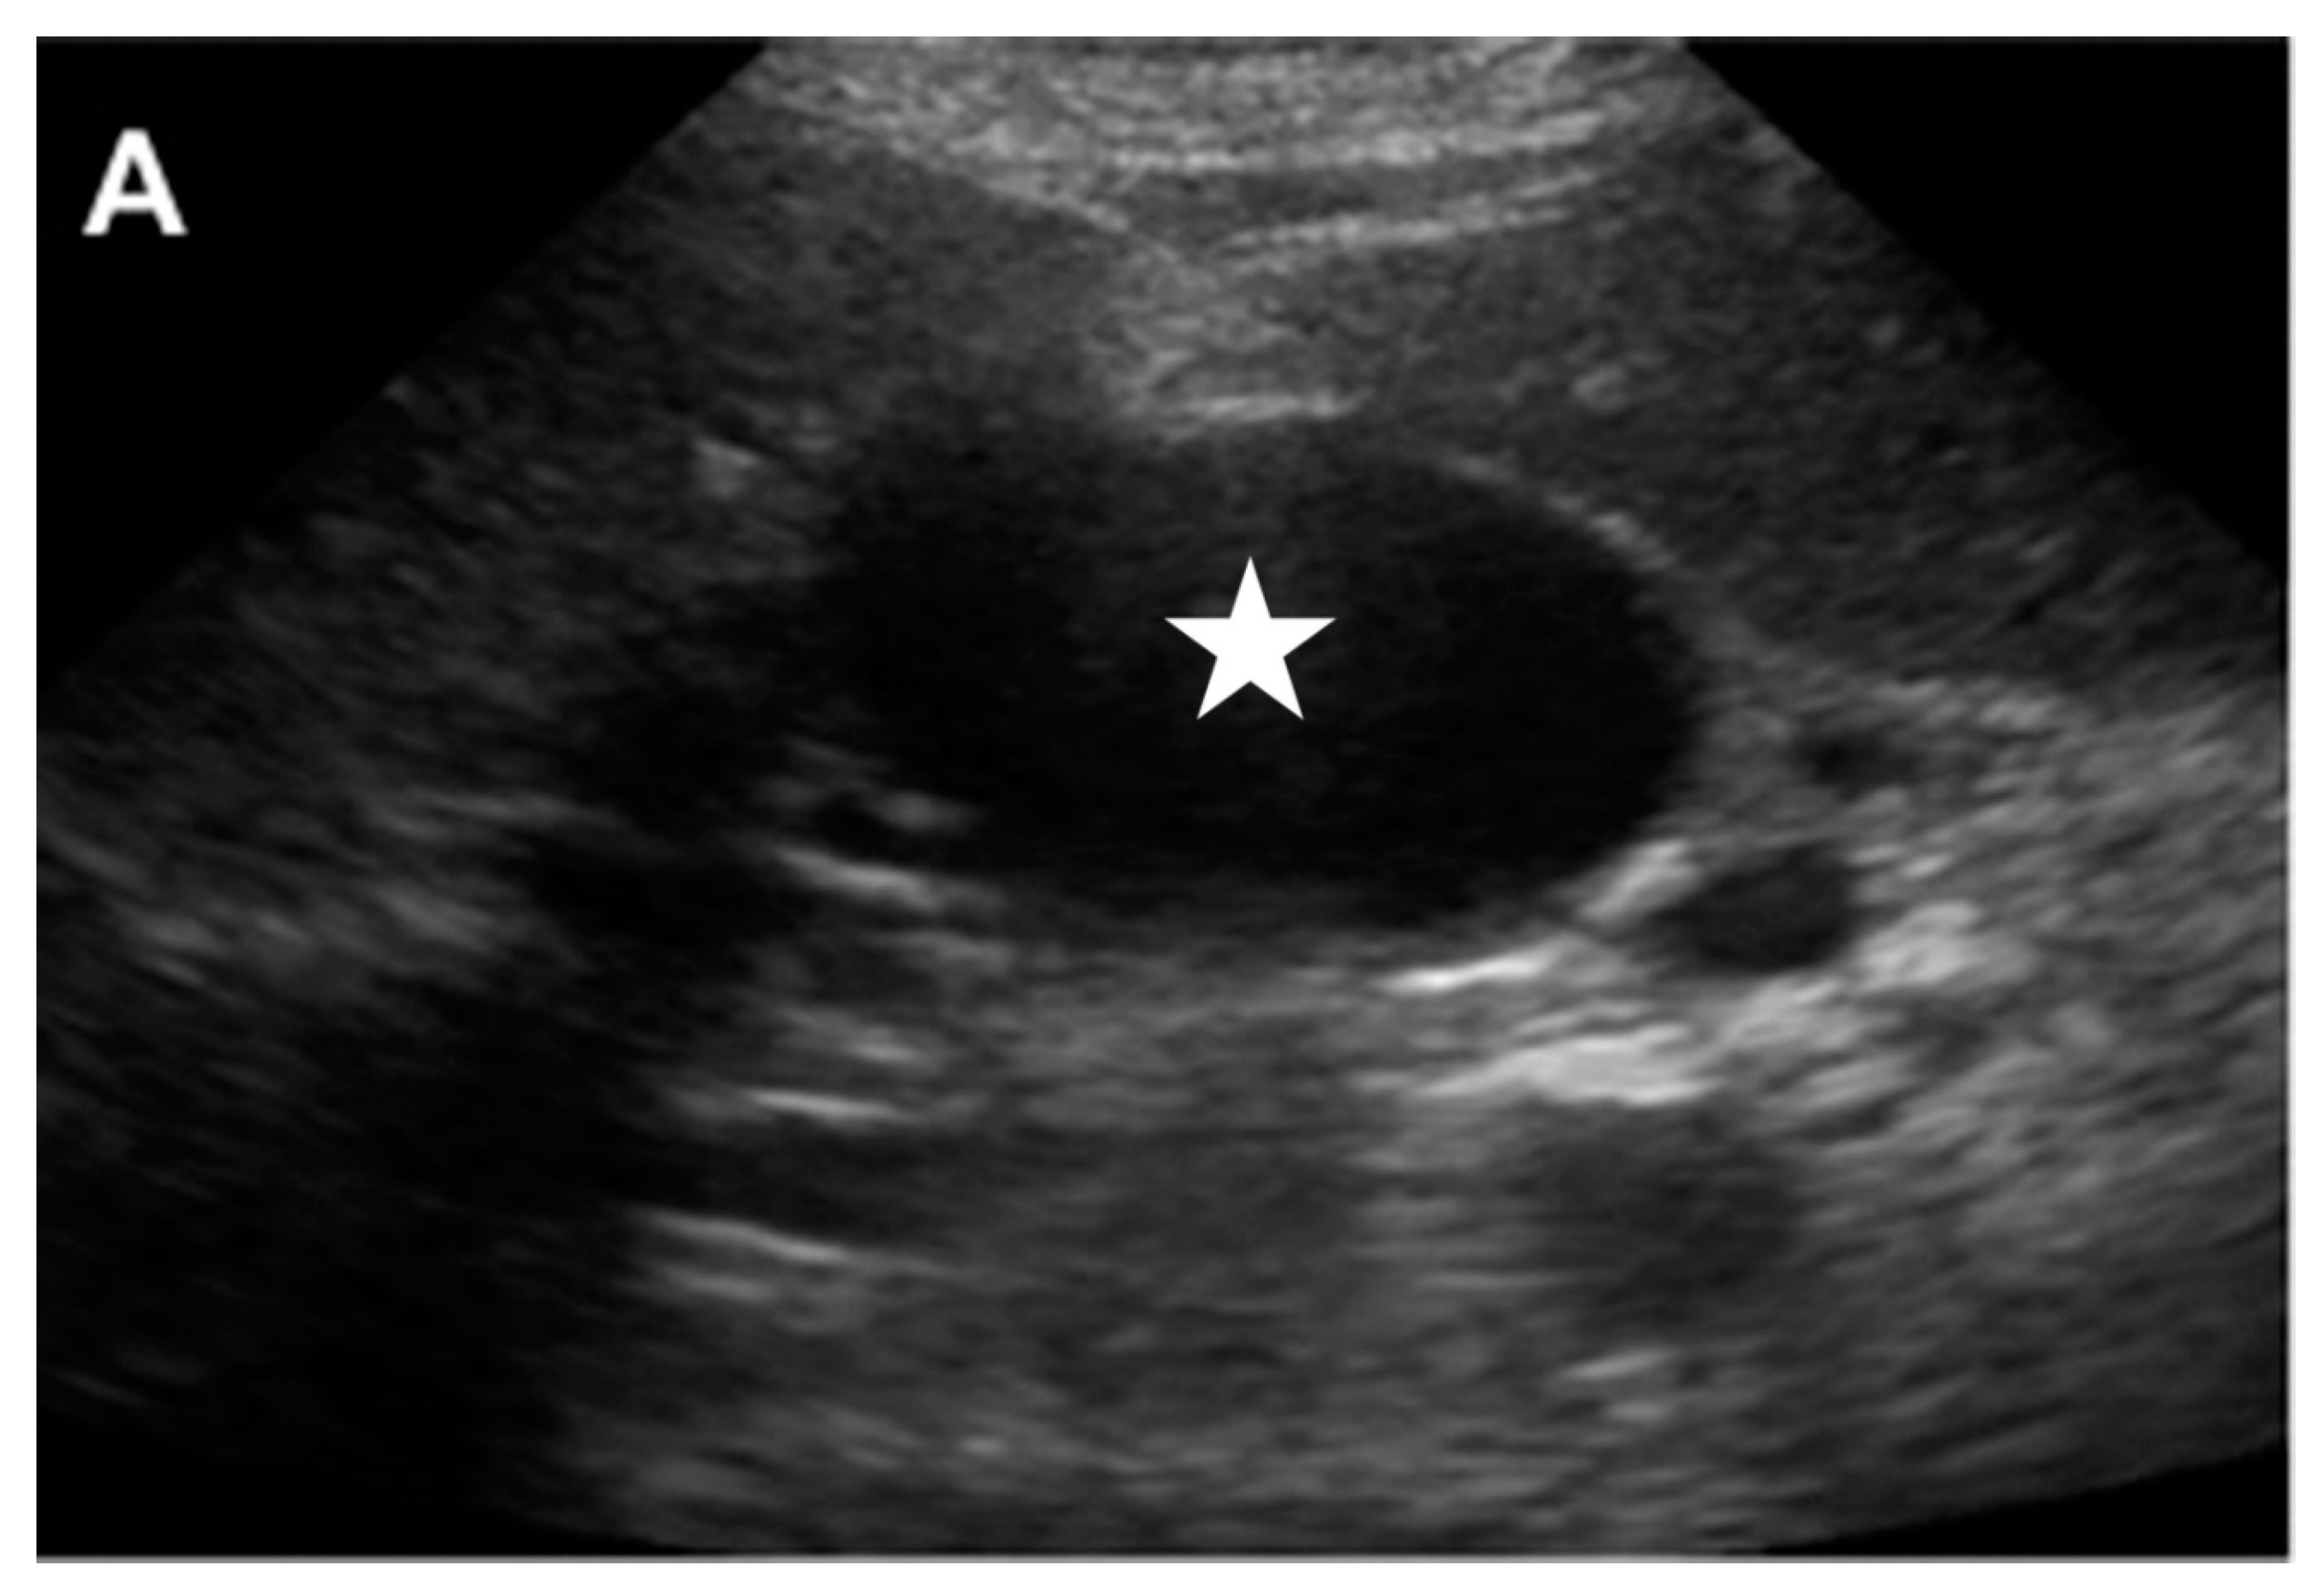

4. GDA Pseudoaneurysm Embolization